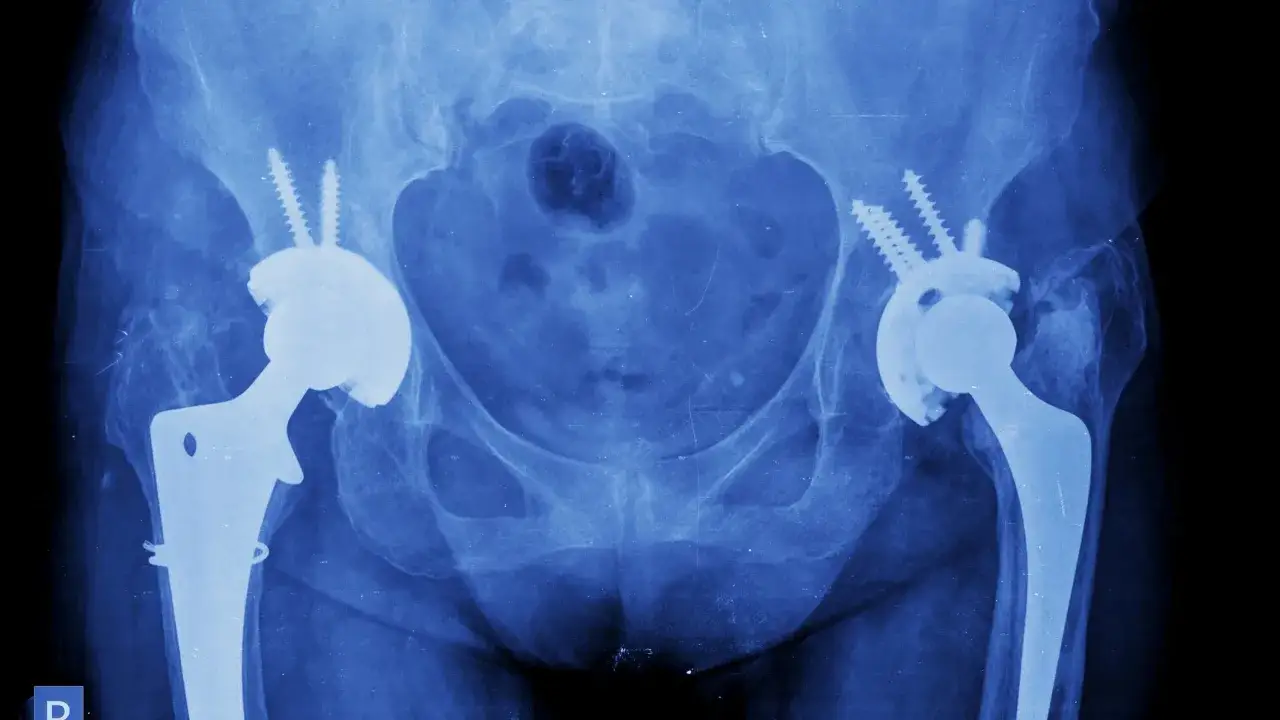

- Rodzaj endoprotezy i metoda operacyjna: Nowoczesne endoprotezy i techniki minimalnie inwazyjne często skracają czas rekonwalescencji, zmniejszając uraz tkanek.